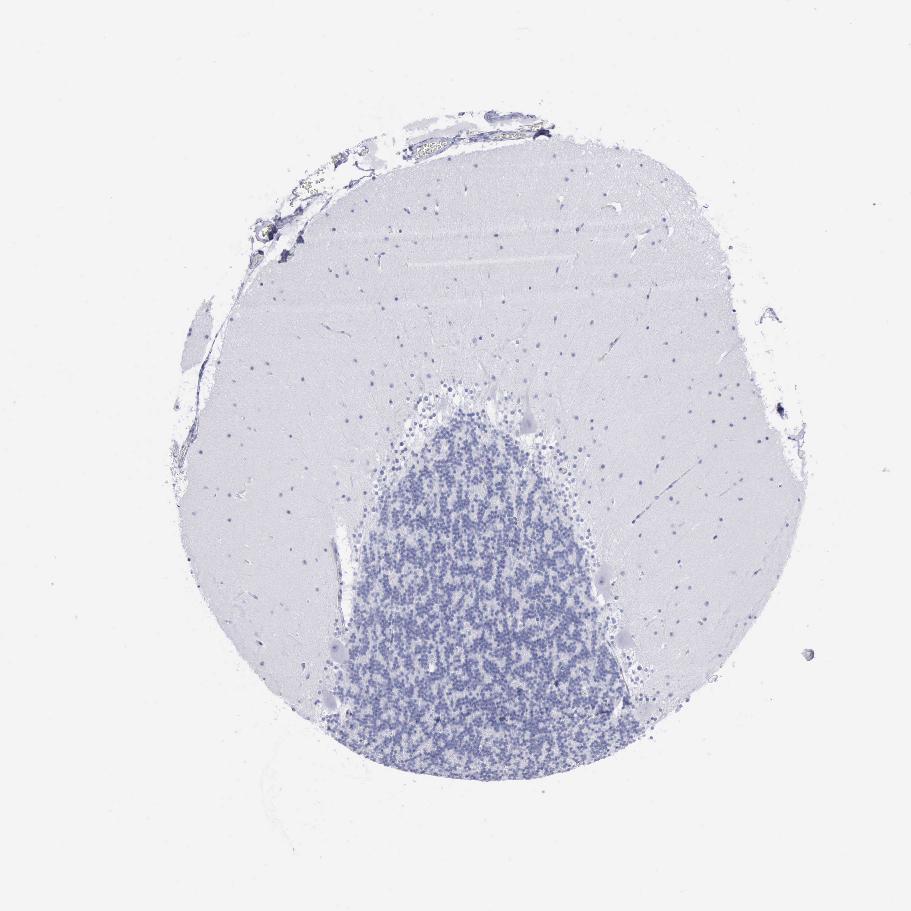

BRAIN CEREBELLUM Show tissue menu

CEREBELLUM - Expression summary

CEREBELLUM - Antibody stainingi

Antibody staining in the annotated cell types in the current human tissue is reported as not detected, low, medium, or high, based on conventional immunohistochemistry profiling in selected tissues. This score is based on the combination of the staining intensity and fraction of stained cells.

Each image is clickable and will lead to virtual microscopy that enables deeper exploration of all samples and also displays staining intensity scores, fraction scores and subcellular localization as well as patient and tissue information for each sample.

Antibody HPA030877Antibody CAB000133

Purkinje cells Not detectedNot detected

Cells in granular layer Not detectedNot detected

Cells in molecular layer Not detectedNot detected